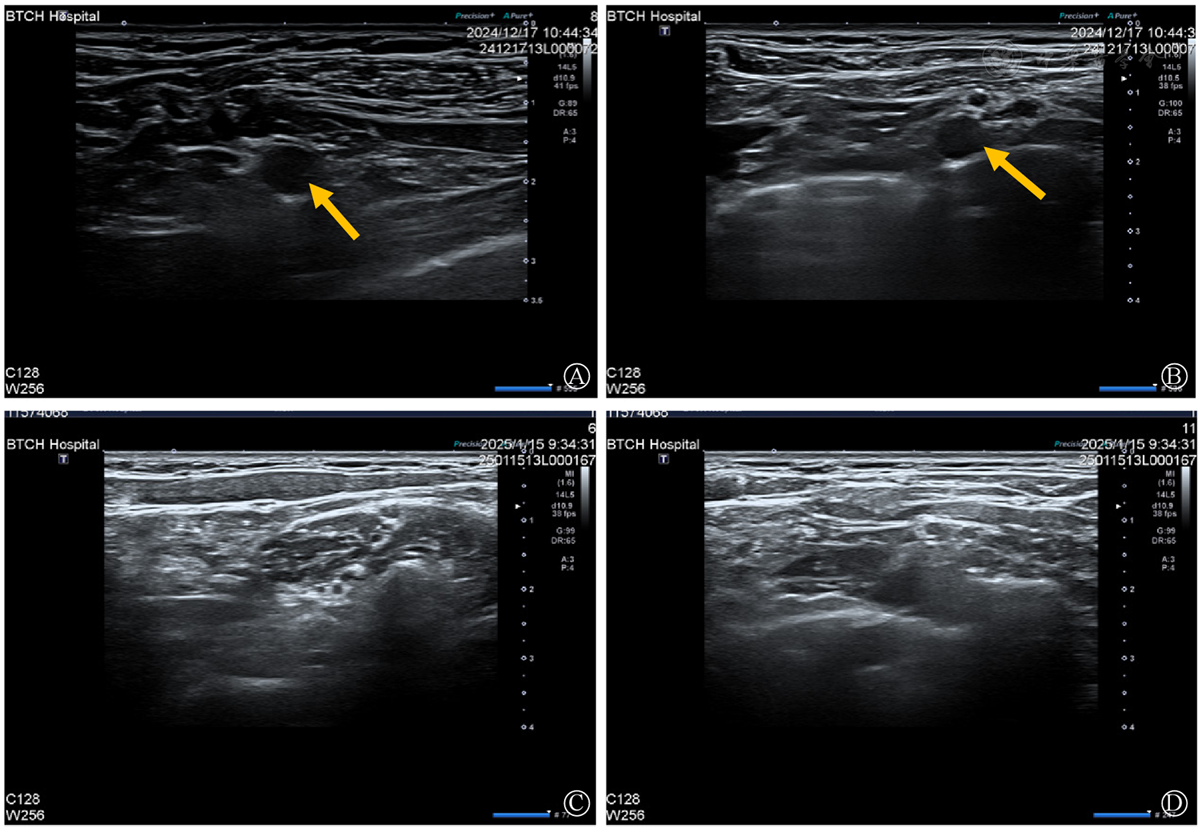

The data of 22 patients diagnosed with cervical spondylosis complicated with brachial plexus neuritis who visited Fuxing Hospital Affiliated to Capital Medical University and Tsinghua Changgung Hospital of Tsinghua University in Beijing from August 2016 to January 2025 were collected. Their onset characteristics, symptoms and signs, imaging (cervical MRI, brachial plexus nerve ultrasound/MRN), and neuroelectrophysiological features were summarized. Moreover, follow up on its comprehensive therapeutic effect.

Among the 22 patients, 16 were male, and 6 were female, aged 43 to 87 years, with disease courses ranging from 10 days to 7 months. All 22 patients presented with acute exacerbation of pain and movement disorders based on chronic neck discomfort, and most of them were accompanied by evident proximal muscle atrophy of the upper limbs. Electromyography confirmed neurogenic damage, mainly due to brachial plexus injury, with a pattern characterized by injury to common motor nerves such as the suprascapular, axillary, and musculocutaneous nerves. After comprehensive treatment, the pain of all patients was significantly relieved. At the 6-month follow-up, 21 patients achieved clinical cure.